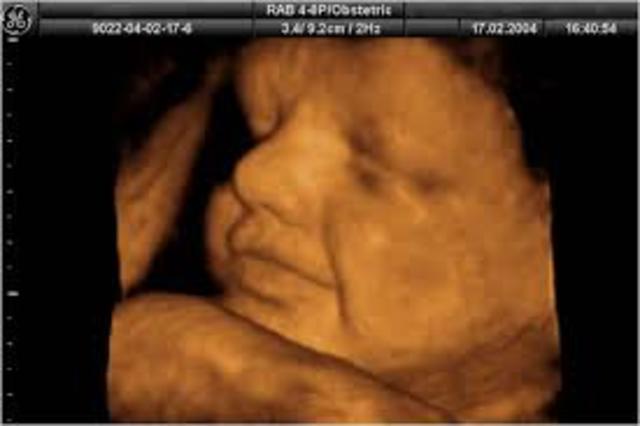

Los riñones de tu bebé producen orina y sus pulmones comienzan a respirar, su cerebro continúa creciendo y las uñas ya llegan a la punta de sus dedos, por lo que deberás cortárselas al poco tiempo de nacer. Su rostro también es más expresivo y a veces sacará la leng